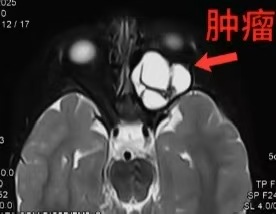

眼眶影像图(箭头所指白色为肿瘤)

影像学显示,肿瘤在幼小眼眶内“野蛮”生长,充满整个眶腔,严重挤压眼球和视神经,分离过程中稍微刺激或者压迫,就可能导致永久失明。更危险的是,肿瘤已撑开眶上裂,随时可能钻进颅内;并已撑开眶下裂、翼腭窝,挤进颞下窝和面深部。最关键的是,翼突受压变形,与颌内动脉紧贴一起。这根动脉一旦破裂,将引起大出血,可迅速导致患儿失血性休克。